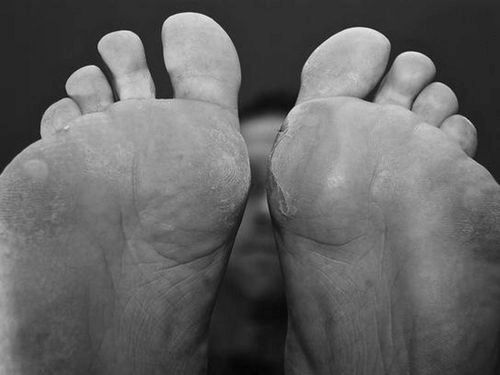

3 способи, як швидко вилікувати мозоль на нозі і ступнях. Лікування і позбавлення наросту в домашніх умовах і клініці

Мозоль - утворення на шкірі, яке доставляє масу незручностей.

Неприємне освіти являє собою зроговіння шкіри, яке не є заразним. Мозолі викликають хворобливі відчуття при будь-яких рухах.

сухі мозолі

Являє собою натоптаний шар відмерлих лусочок шкіри, товщина яких збільшується постійно. Може з'явитися, як простий пухир, який лопається, а висохла шкіра під ним стає ороговілої.

При великій товщині мозолі лопаються і покриваються хворобливими тріщинами. Можливо нагноєння тріщин, що з'явилися.